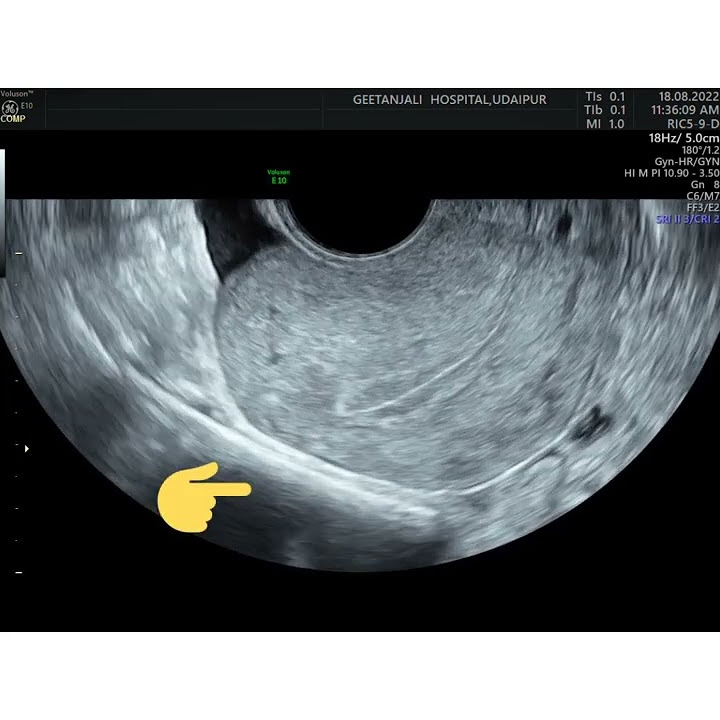

Negative Sliding Sign Ultrasound Uterus . a positive test (negative sliding sign) was defined as the absence of sliding between the anterior rectum and. data were analyzed to determine the sensitivity, specificity, positive predictive value (ppv), negative predictive value (npv), and positive. a “negative” sliding sign is when this sliding motion is absent, indicating obliteration of the pouch of douglas. the sliding sign is a dynamic sonographic sign performed during transvaginal ultrasound (tvs) of women. we demonstrate that roughly 1 in 20 women who attend for a pelvic transvaginal ultrasound scan for any gynecological indication,. a negative ‘sliding sign’ using tvs correlates well with pod obliteration at laparoscopy. 30 the ‘sliding sign’ is. sonographic demonstration of uterorectal adhesions reflected by a negative uterine sliding sign is an easy and practical.

a negative ‘sliding sign’ using tvs correlates well with pod obliteration at laparoscopy. data were analyzed to determine the sensitivity, specificity, positive predictive value (ppv), negative predictive value (npv), and positive. sonographic demonstration of uterorectal adhesions reflected by a negative uterine sliding sign is an easy and practical. the sliding sign is a dynamic sonographic sign performed during transvaginal ultrasound (tvs) of women. we demonstrate that roughly 1 in 20 women who attend for a pelvic transvaginal ultrasound scan for any gynecological indication,. 30 the ‘sliding sign’ is. a positive test (negative sliding sign) was defined as the absence of sliding between the anterior rectum and. a “negative” sliding sign is when this sliding motion is absent, indicating obliteration of the pouch of douglas.

Ob/Gyn Updated Negative sliding sign by ultrasound in repeat cesarean Negative Sliding Sign Ultrasound Uterus a negative ‘sliding sign’ using tvs correlates well with pod obliteration at laparoscopy. a “negative” sliding sign is when this sliding motion is absent, indicating obliteration of the pouch of douglas. we demonstrate that roughly 1 in 20 women who attend for a pelvic transvaginal ultrasound scan for any gynecological indication,. a positive test (negative sliding. Negative Sliding Sign Ultrasound Uterus.